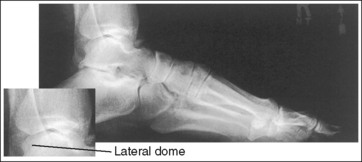

The foot is in a lateral projection. The talar domes are superimposed, the tibiotalar joint is open, and the distal fibula is superimposed by the posterior half of the distal tibia.

• Talar domes. The domes of the talus are formed by the most medial and lateral aspects of the talar's trochlear surface. On a lateral foot projection, they appear as domed structures that articulate with the tibia. On a properly positioned lateral foot projection, the talar domes should be superimposed and appear as one and the tibiotalar joint should be open. When the lateral foot is mispositioned, the domes are individually demonstrated, and they obscure the tibiotalar joint. Proximal-distal misalignment of the domes results from poor knee and lower leg positioning, and AP misalignment of the domes results from poor foot positioning.

When viewing a lateral foot projection that demonstrates one of the talar domes proximal to the other, evaluate the height of the longitudinal arch and the degree of narrowing or widening of the talocalcaneal joint to determine which dome is the proximal dome. If the navicular bone is superimposed over more of the cuboid than expected and the talocalcaneal joint is narrowed, the lateral dome is the proximal dome; if the navicular bone is superimposed over less of the cuboid than expected and the talocalcaneal joint is wider, the medial dome is the proximal dome.

• Effect of foot positioning on AP talar dome superimposition. To demonstrate accurate AP alignment of the talar domes, position the lateral surface of the foot parallel with the IR. If this surface is not parallel with the IR, one of the talar domes is demonstrated anterior to the other. When the leg is rotated more than needed to place the lateral foot surface parallel with the IR, as shown in Figure 6-29, the medial talar dome is demonstrated anterior to the lateral talar dome (see Image 20). If the leg is not rotated enough to place the lateral foot surface parallel with the IR, as shown in Figure 6-30, the medial talar dome is demonstrated posterior to the lateral talar dome (see Image 21).

When viewing a lateral foot projection that demonstrates one of the talar domes anterior to the other, evaluate the position of the fibula in relation to the tibia to determine how to reposition the patient. On most lateral foot projections with accurate positioning, the fibula is positioned in the posterior half of the tibia. If the fibula is demonstrated more posteriorly than this relationship on a lateral foot projection with poor positioning, the medial talar dome is anterior and the patient was positioned with the forefoot depressed and the heel elevated (leg externally rotated), as shown in Figure 6-29. If the fibula is demonstrated more anteriorly than this relationship, the medial talar dome is posterior and the patient was positioned with the forefoot elevated and the heel depressed (leg internal rotation), as shown in Figure 6-30.